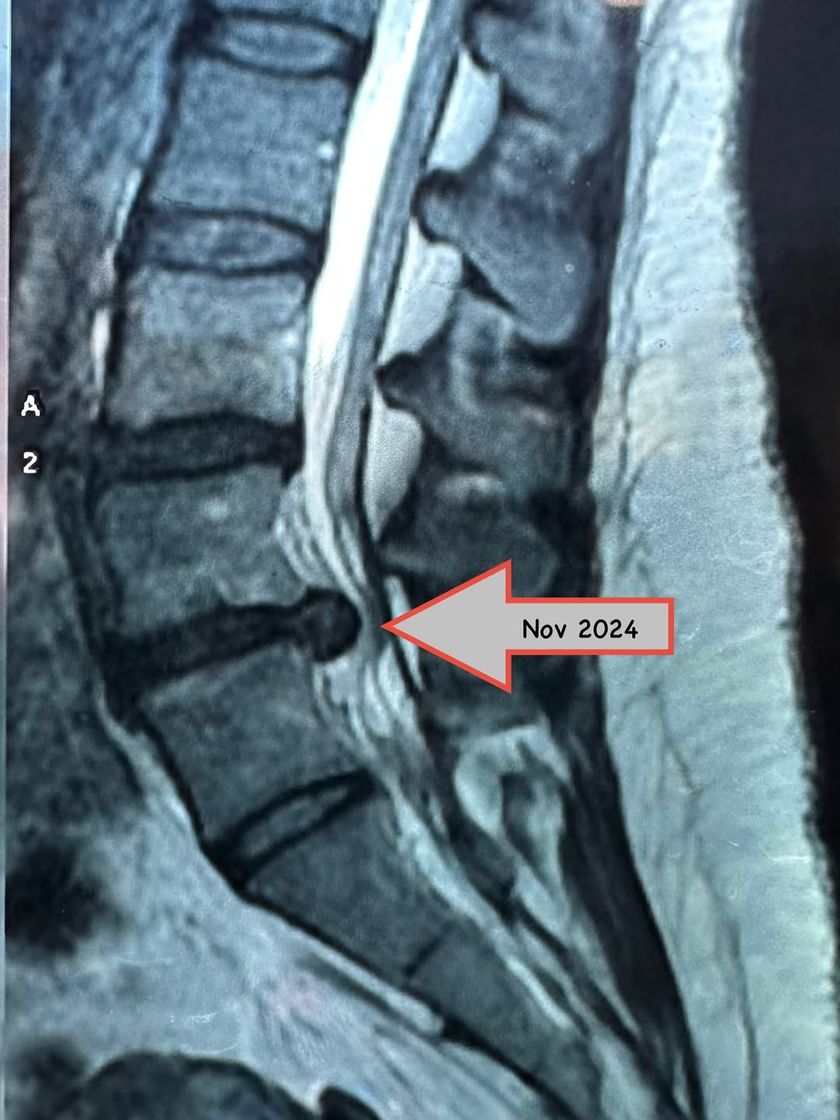

Real Results: Non-Surgical Recovery

If you have been told surgery is your only option for issues like a disc bulge or sciatica, let's talk first. I specialize in non-surgical recovery programs that combine targeted manual therapy with progressive exercises to help your body heal naturally.